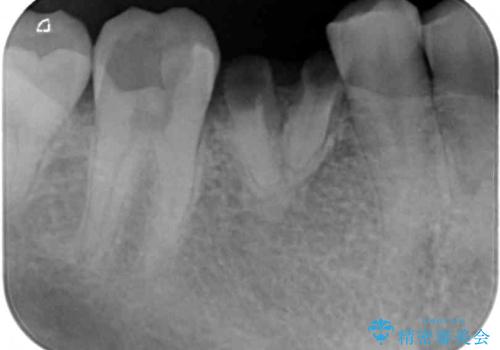

- 奥歯が痛く、放置した虫歯があるとのことで来院された患者様です。

全体的に汚れが多く、歯の表面の脱灰が全体的に認められましたが、まずは奥歯の虫歯治療から行うこととしました。

根っこだけとなっている歯は抜歯をし、奥の大きな虫歯となっている歯は、神経を取り除く可能性を考慮しながら処置を進めて行くこととしました。

抜歯部分の治癒を待つ間に、全体的な汚れの多さを改善する指導と処置を進め、その後オールセラミックブリッジにて補綴治療を行うこととしました。